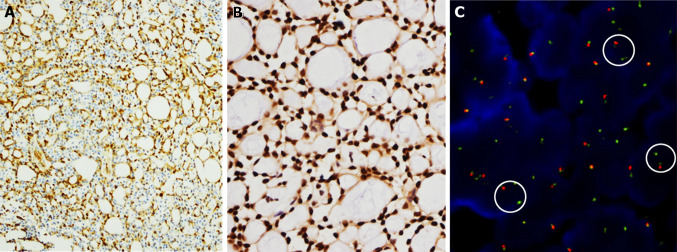

Fig. 7.

The esophageal adenoid cystic carcinoma (AdCC) is composed of impacted cells with scant cytoplasm, forming solid (left) and cribriform structures (right)

Fig. 8.

Immunohistochemical and FISH results of the esophageal AdCC. a The myoepithelial neoplastic cells are positive for Calponin (Calponin, CALP, zhongshanjinqiao, undiluted). b MYB (Anti-v-Myb + c-Myb (phospho S12), Abcam, 1:200) is diffusely positive. c FISH using a break-apart probe shows translocation of MYB gene (in the circle). The ZytoLight SPEC dual color break apart probe (PL100) is composed of ZyGreen (exciting 503 mm/ emission 528 mm) labeled polynucleotide, which target sequences mapping in 6q23.2–23.3 (chr6:134,840,690–135,483,752) proximal to the MYB breakpoint region. ZyOrange (exciting 547 mm/ emission 572 mm) labeled polynucleotide, which target sequences mapping in 6q23.3 (chr6:135,728,667–136,390,142) distal to the MYB breakpoint region